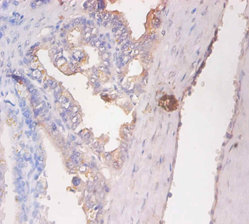

DescriptionCD59 Polyclonal Antibody. Unconjugated. Raised in: Rabbit.

ApplicationELISA, IHC, IF; Recommended dilution: IHC:1:20-1:200